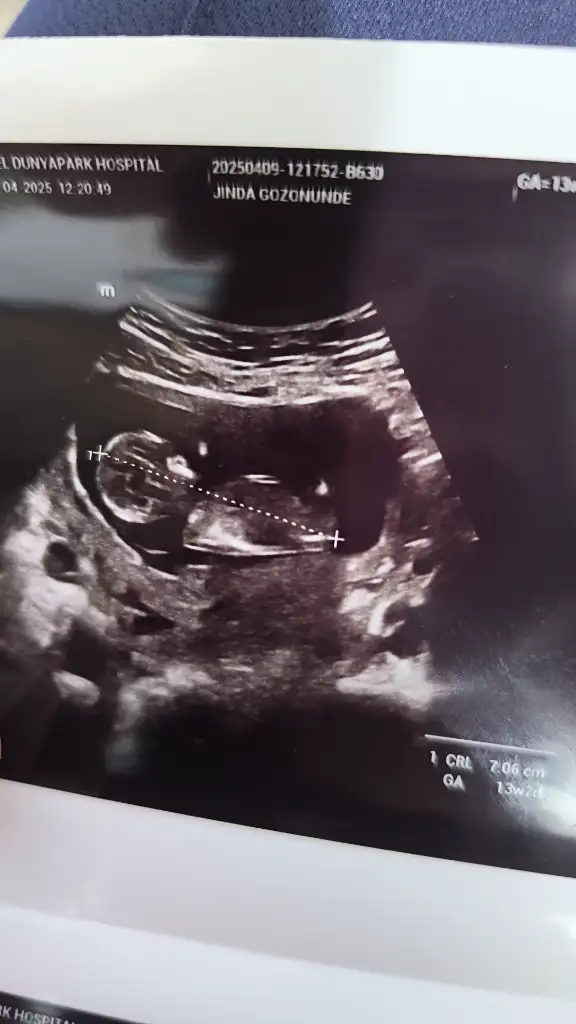

Erkek gibi geldi bana.2 li taramadan ultrason goruntum tahmin edebilecek olan var mi Eki Görüntüle 3575150

Bana da bakar mısınız rica etsemKız gibi görünüyor

Banada bakarmısınız lütfen tahminde bulunurmusunuzKuzum nub gözükmüyor tam o yüzden emin olmamakla birlikte benim kızıma benzettim kız diyim o yüzden

Başka açıdan var mı burda pek tahmin yürütemedimBanada bakarmısınız lütfen tahminde bulunurmusunuz

Sadece bu varBaşka açıdan var mı burda pek tahmin yürütemedim